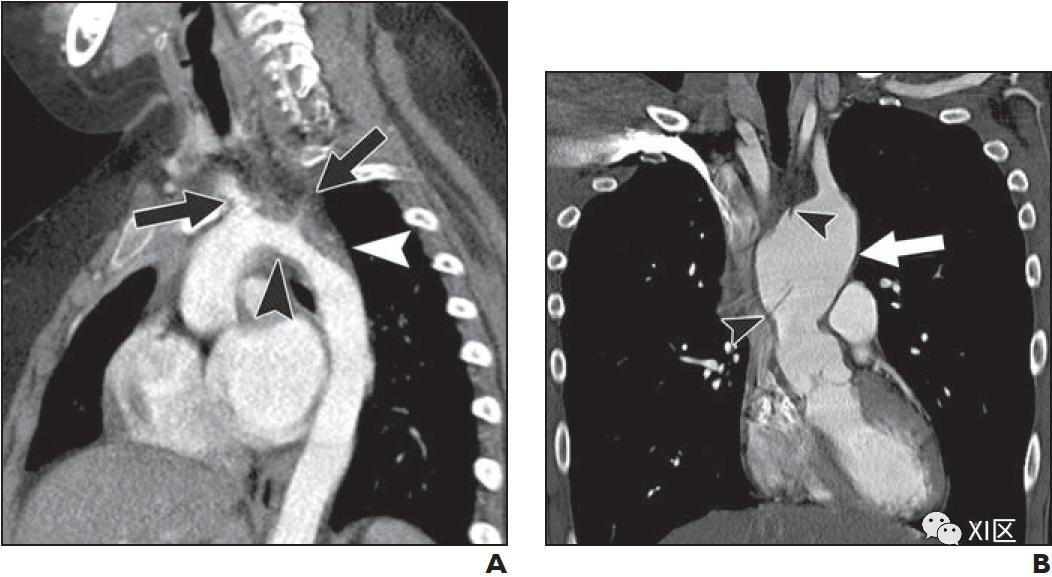

肺动脉吊索不是一个完整的血管环,但常有类似的气喘、咳嗽和反复肺部感染的症状。而正常情况下,左肺动脉(LPA)起源于主肺动脉,并在左主支气管上方和后方走行,而在肺吊索中,LPA来自右肺动脉,穿过右主支气管,然后在气管和食道之间穿过,到达左肺门(图5)。肺CTA对完全评估肺动脉吊索特别有帮助,因为它常常伴有气管支气管树的异常形态、气管支气管软化和其他异常的肺血管结构(图5)。